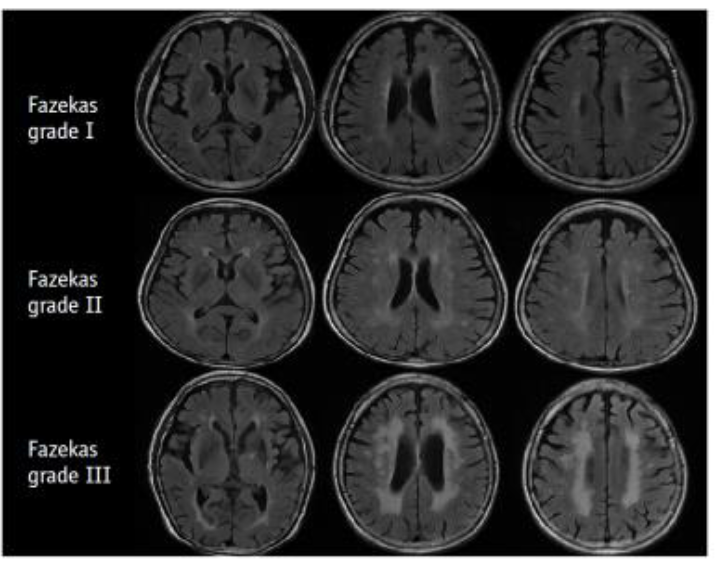

認知症のの診断診断に用に用用いるいる画像 CT MRI SPECT PET •脳血管性病変のの評価評価 •多発性のもの •大大きいものきいもの •両側性のもの •PVLのの評価評価 •小小さなさな病巣のの判定判定 •海馬のの評価評価 •PVHのの評価評価.

CT、MRIによる形態画像診断では、脳の萎縮、脳梗塞・脳出血、脳腫瘍、水頭症、慢性硬膜下血腫などの有無を調べます。 アルツハイマー型認知症では、脳の全般的萎縮と海馬(矢印部分)の萎縮(脳溝拡大、脳室拡大、側脳室下角拡大など)が著明である。 連載第11回で示したものは水平断で、ここでは冠状断を示した 本書で紹介している治療法等は、著者が臨床例. 近畿大学病院放射線診断科で認知症に対する画像検査を受けられた患者様・ご家族の皆様・・・ お知らせ 近畿大学病院放射線診断科(以下、当科)では、「認知症患者の診療情報を用いた認知症患者データベースの構築」という臨床研究を行っています。. 認知症ドッグで軽度認知症を早期発見して適切な対策を行うことにより、症状の進行を阻止することが可能となり、認知症の症状が最後まで出ずにすむケースもあります。 検査内容 1心理学的検査(認知力・記憶力) 2mri検査.

連載 自動車産業人向けヘルス ケア 認知症は運転ができなくなる病気 5 脳血管障害性認知症の患者さんとmri画像所見 企画 解説 紙面記事

脳血管性認知症の今昔 新潟市医師会報より

認知症の画像診断 その1 Iroop